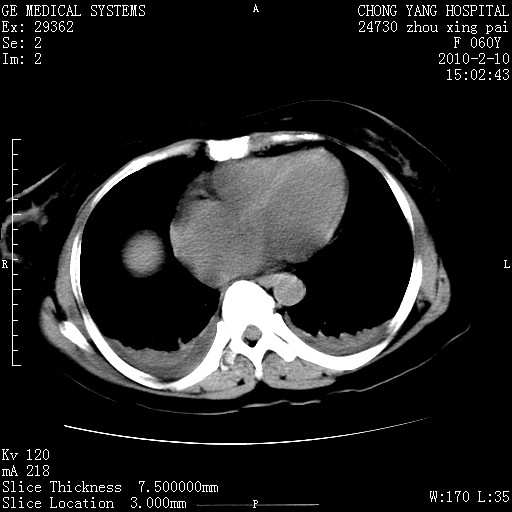

标题: CT24682:F60Y 腹痛 其它不详 [打印本页]

标题: CT24682:F60Y 腹痛 其它不详

1)胆总管末端梗阻,不排除结石所致可能。2)胰腺炎。3)慢性胆囊炎可能。4)左侧输尿管上段扩张。5)少量腹水。6)双侧少量胸腔积液,伴两下肺部分肺萎陷。

1)胆囊炎。2)胆源性胰腺炎。3)右肾周筋膜增厚,肾旁前间隙积液。4)左侧输尿管上段扩张。5)少量腹水。6)双侧少量胸腔积液,伴两下肺部分肺膨胀不全。

1)胆总管末端梗阻。2)胰腺炎。3)慢性胆囊炎可能。4)左侧输尿管上段扩张。5)少量腹水。6)双侧少量胸腔积液,伴两下肺部分肺萎陷。